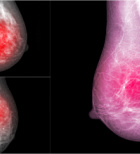

הסרת סרטן השד - תמונת המחשה

הסרת סרטן השד רבים מכירים את הטיפולים האסתטיים בכירורגיה פלסטית כדוגמת הזרקות, בוטוקס, הרמת עפעפיים ו...